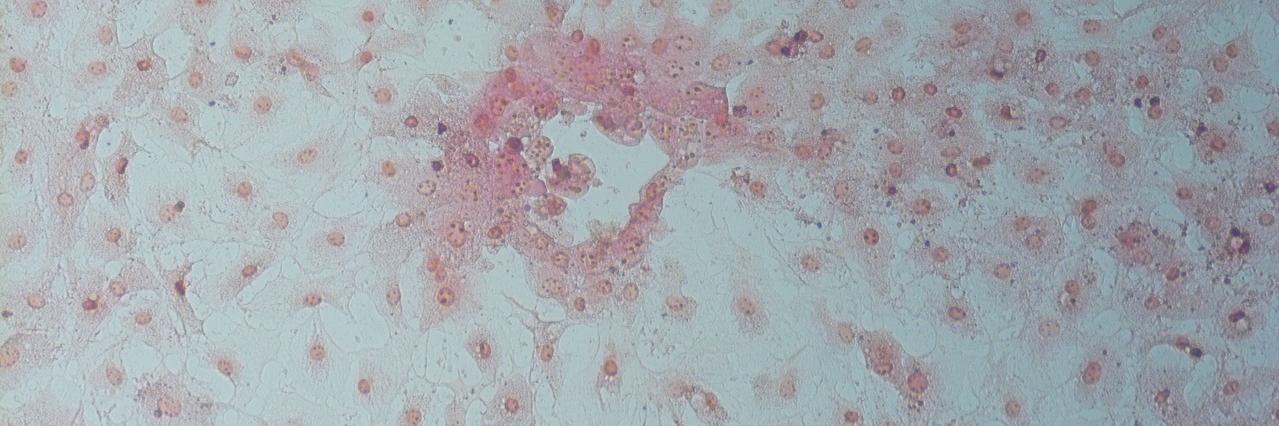

Colostrum from SARS-CoV-2 infected mothers, the best protection against COVID-19 infection #JCL-P-15" target="_blank" rel="nofollow noopener">journals.lww.com/pidj/fulltext/…